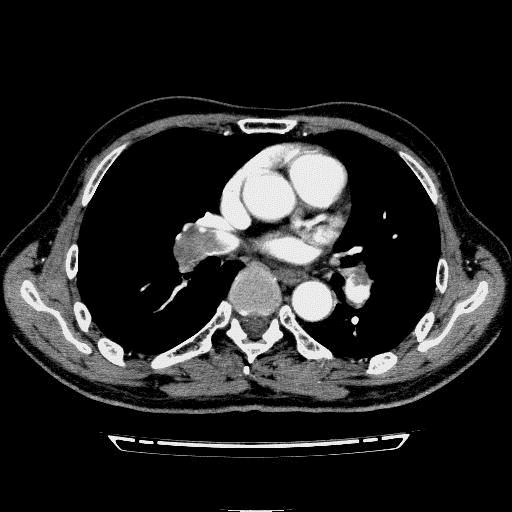

问题 病历摘要: 患者女性,83岁,活动后气促10天,伴心悸、咳嗽,咳少许白粘痰,感左侧胸痛,呈压榨样,与呼吸有关,但无放射痛,并发热,体温最高37.9℃,无明显规律性,无咯血、畏寒等。既往有系统性红斑狼疮病史,有吸烟史20年,已经戒烟20年。1月前始自觉双下肢易疲劳,但活动不受限。体查:T37.7℃,左肺可闻及啸鸣音和少许细湿啰音,心率123bpm,律齐,P2>A2,未闻及杂音。双下肢无水肿。 肺血栓栓塞症的血栓大部分来源于何处? 提示:双下肢静脉超声见双下肢静脉血栓形成

选项 A.上腔静脉 B.右心腔 C.下肢近端深静脉 D.盆腔静脉 E.颈内静脉 F.锁骨下静脉 G.肺动脉

答案 C